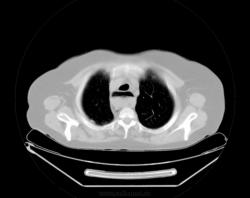

При профилактическом исследовании у женщины 75 лет выявлены изменения в легких и средостенье. Выполнена КТ. Ваше мнение, коллеги?

На сколько я понимаю это пищевод с содержимым, вот только не понятно на последнем скане, режим бы другой.

Но там была ахалазия. А по рентгенограммам, мне, что-то кажется, что в данном случае аорта.

Почему провокация?! У меня что, имидж такой? о провокациях я так сразу и пишу в заголовке... Нет здесь ни провокации, ни загадки. Действительно, ахалазия кардии, пневмофиброз в легких, по-видимому метатуберкулезный. А случай мне показался интересным, потому как эта ахалазия имеет 50 лет анамнеза без лечения